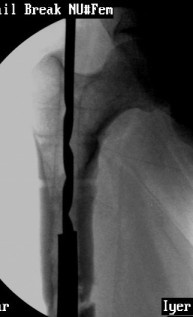

VMI-I am enclosing pictures of how I had to do it once. The C arm picture shows the first attempt to try and jam a solid reamer into the nail and trying to pull it out. Did not work.

The second picture shows a plain guide wire inserted thro the nail, prograde, hammered out thro the distal femur, out thro the skin. A beaded guide wire being railroaded on the earlier G W into the distal end of the nail.

This is the C-arm picture before attemting to pull out thro the proximal end by hammering on a chuck.

Did not work out. The nail was a slotted one. The guidewire split the slot and came out but not the nail. Ultimately as mentioned in an earlier mail, I had to introduce a cannulated nail from distally threadind on the guide wire and hammer on the stuck nail and finally got it out

This picture shows the beaded guide wire into the nail from its distal end.